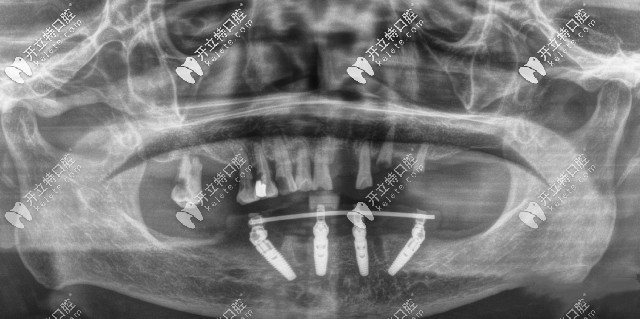

广州广大口腔ALLON4半口种植牙CT片

闲话不多说,大家还是来亲眼见识一下广州广大口腔的种植牙怎么样吧: